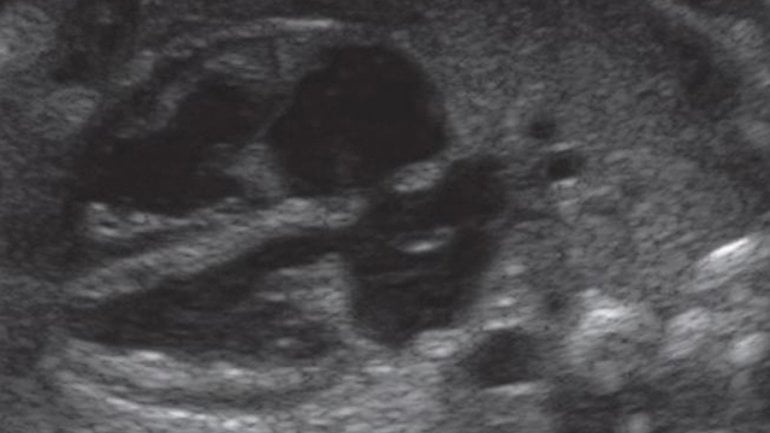

Ultraschall 39. SSW

Auf diesem Bild sind deutlich die vier Herzkammern und die Herzklappen zu erkennen. Das Herz schlägt jetzt schon seit 33 Wochen unablässig, was auf dem CTG gut zu hören ist.